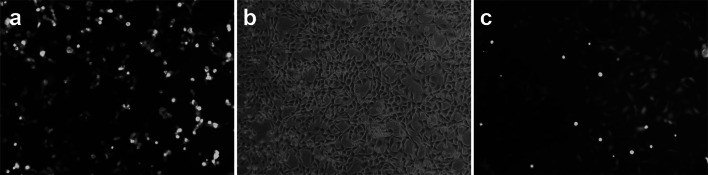

The rhNGF-β adenovirus was multiplied and purified based on a previously reported protocol [7]. The NGF-Adenovirus (NGF-Ad) shuttle vector and pJM17, a plasmid containing the entire adenoviral genome, were co-transfected into 293 cells to generate homologous recombination between the adenovirus genome sequences (Fig. 1a). The constructed replication-incompetent NGF-Ad was isolated as a single plaque to remove wild adenovirus.

Single treatment of mesenchymal stem cells. a Multiplication and purification of rhNGF-β adenovirus. NGF-Ad was co-transfected into 293 cells. b Mesenchymal stem cell culture. c rhNGH- β gene transfection into BMSCs. BMSCs infected with rhNGF- β adenovirus were monitored for GFP expression under a fluorescence microscope 24 h after infection (original magnification × 20)

rhNGH- β gene transfection into BMSCs

Passage zero BMSCs were seeded at a density of 1 × 104 cells in a 100 mm dish for 24 h. Then, 2 ml of serum-free α-minimum essential medium (α-MEM) was added and the cells were incubated at 37 °C for 60 min. The BMSCs were then infected with rhNGF-β Ad at a multiplicity of infection (MOI) of 70. After removing the media, the cells were washed once with α-MEM and then re-cultured in normal medium for 24 h for green fluorescent protein (GFP) expression. The BMSCs infected with rhNGF- β adenovirus were monitored for GFP expression under a fluorescence microscope 24 h after infection (Fig. 1b, c). When the number of GFP-positive cells became more than 80% of the total number of cells, the cells were used in the experiment.

After 24 h, most of the BMSCs were transfected with rhNGF-β adenovirus, and GFP expression was observed under a fluorescence microscope without any changes in cell morphology (Fig. 1c).